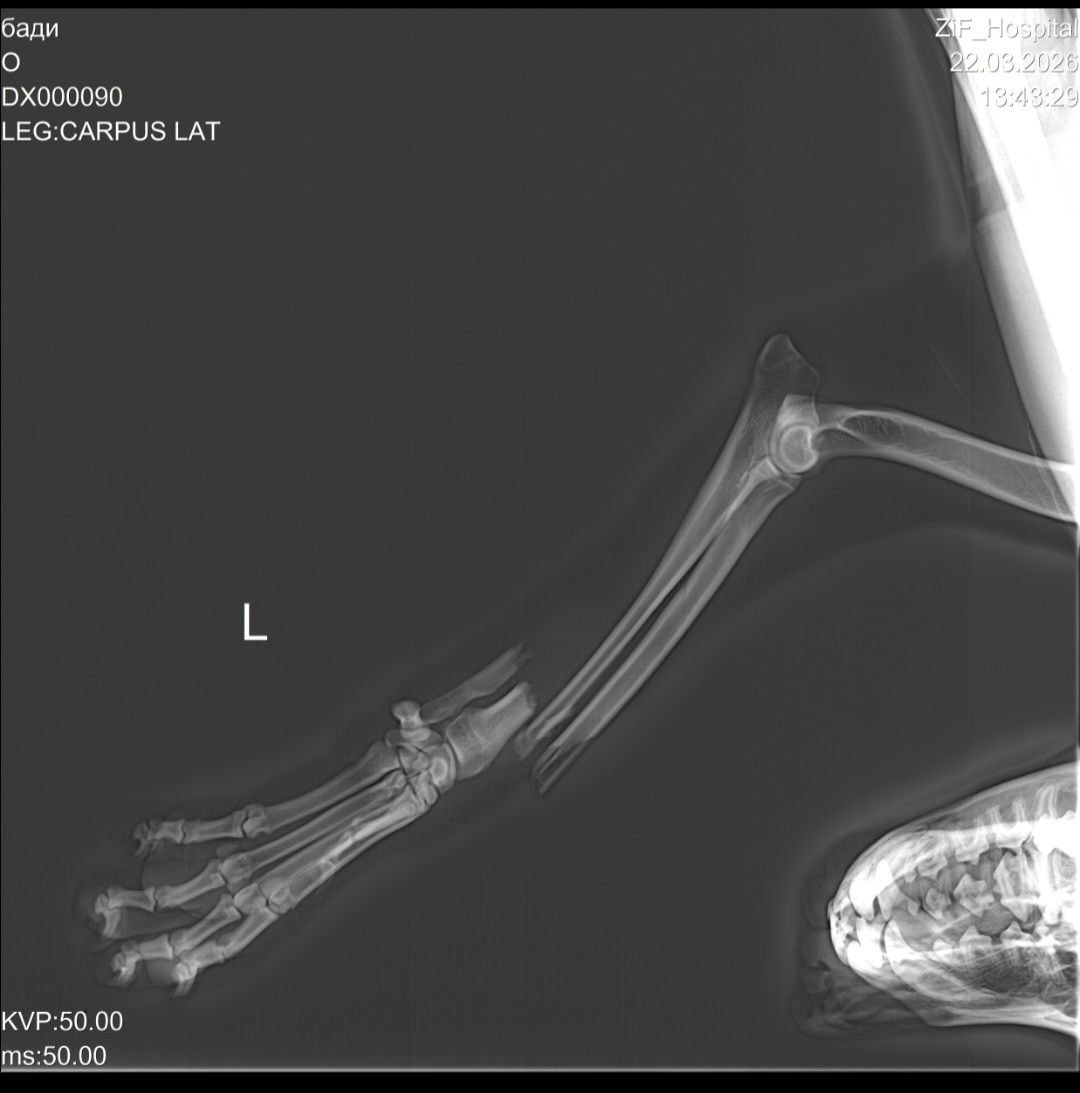

Машина переехала лапу и уехала.

Открытый перелом. Собака в таком тяжёлом состоянии с болями находится уже четыре дня. Все время плачет.

Бади нужно лечь на стационар, чтобы хоть как-то его стабилизировать перед операцией, тк уже на лапе некроз мягких тканей.